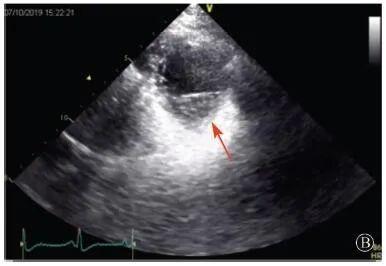

患者入院后無特殊不適,心率70次/min,血壓110/60 mmHg,心功能Ⅱ級。查血常規(guī):血紅蛋白139 g/L,白細胞7.39×109/L,血小板221×109/L。尿常規(guī)、便常規(guī)+潛血均正常。生化:丙氨酸氨基轉(zhuǎn)移酶38 U/L,白蛋白47 g/L,鉀3.9 mmol/L,肌酐(酶法)65 μmol/L,總膽固醇3.52 mmol/L,低密度脂蛋白膽固醇2.08 mmol/L。CK:1256→487 U/L,CK-MB 9.7→3.8 μg/L,cTnI 85.90→68.50 pg/ml。N末端B型利鈉肽原70 pg/ml。CK同工酶電泳:肌酸激酶MM質(zhì)量100.0%(此時CK-MB已正常)。血沉1 mm/第1小時,高敏C反應(yīng)蛋白1.61 mg/L;補體:C3 0.876 g/L,C4 0.174 g/L。免疫球蛋白:IgG 9.52 g/L,IgA 1.73 g/L,IgM 0.62 g/L。血清蛋白電泳未見M蛋白。糖化血紅蛋白5.1%。乳酸(運動前)1.1 mmol/L,乳酸(運動中)6.6 mmol/L,乳酸(運動后)7.8 mmol/L。肌炎抗體譜:抗PM-SCL75(+),余均(-)。心電圖:aVL、V5、V6導聯(lián)T波倒置(圖2)。冠狀動脈CT未見明顯異常。超聲心動圖:左室舒張末內(nèi)徑55 mm,左室收縮功能減低,心尖部、左室壁普遍運動減低,以左室下后壁為著,左室下后壁肌小梁明顯增多可見隱窩,疏松層與致密層之比為1.7;左室射血分數(shù)(雙平面)45%;右冠狀動脈開口6.5 mm,開口處未見明確瘤樣擴張(圖3)。

協(xié)和疑難︱第67例:臨床表現(xiàn)胸痛伴肌酸激酶升高

A:胸骨旁長軸平面,左室舒張末內(nèi)徑略增大,室壁無明顯增厚;

B:胸骨旁左室短軸切面心尖水平,可見心肌肌小梁增多,其內(nèi)可見隱窩(箭頭所示)

圖3 患者入院后超聲心動圖